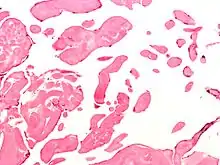

يتم إيجاد وَتَشخيص ورم النسيج المرن الليفي الحليمي عادةً عن طَريق التصوير التشخيصي الطبي، ويتم تَأكيد التشخيص عن طريق علم الأمراض، أما في علم الأنسجة فإنَّ ورم النسيج المرن الليفي الحليمي يمتلك حليمات مُتفرعة لا وعائية تتكون مِن كولاجين، وتكون مُغطاة ببطانة غشائية.